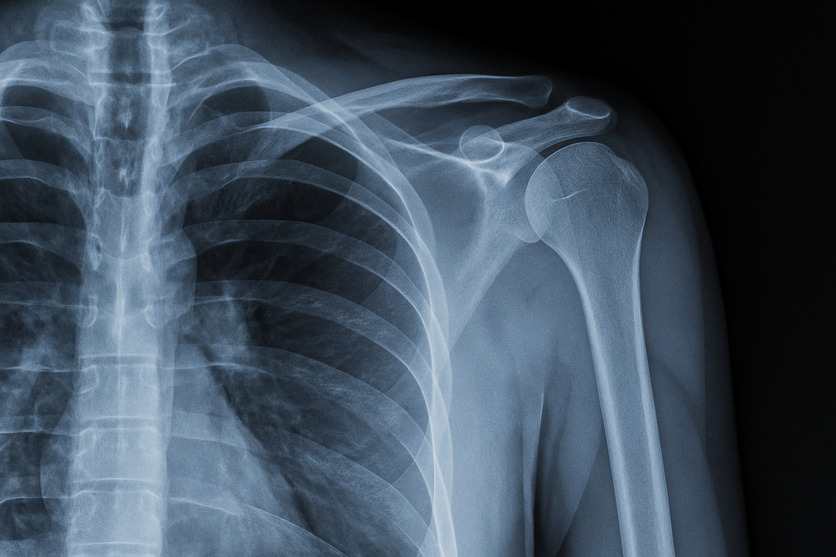

La radiografia della spalla è un esame piuttosto semplice, non invasivo e assolutamente non doloroso. Un apparecchio radiografico invia onde elettromagnetiche (radiazioni) attraverso il corpo. Queste onde creano un'immagine che verrà gestita su una pellicola radiografica o su un sensore radiografico digitale. Nel corso della radiografia il medico acquisisce immagini della spalla da più angolazioni e posizioni.

Poiché le radiazioni non attraversano le ossa, queste sulla radiografia tendono ad apparire bianche. Di contro, altri tessuti, come muscoli o tendini, lasciano transitare una parte delle radiazioni; pertanto, possono manifestarsi attraverso il colore grigio o nero.

Per comprendere bene il funzionamento di questo esame è importante conoscere, quantomeno per sommi capi, l'anatomia della spalla. Parliamo, infatti, dell'articolazione più mobile del corpo e che, dunque, può muoversi in varie direzioni. Pertanto, una radiografia della spalla tenderà ad evidenziare le ossa che compongono questa articolazione e cioè:

- Omero, osso del braccio;

- Acromion, osso che sporge dalla scapola);

- Scapola, osso che si collega all'omero;

- Clavicola, osso che si collega all'acromion;

- Apofisi coracoide, osso a forma di uncino che sporge dalla scapola.

Attraverso la radiografia è, dunque, possibile esaminare le dimensioni, la posizione e la forma di ciascuna di queste ossa.